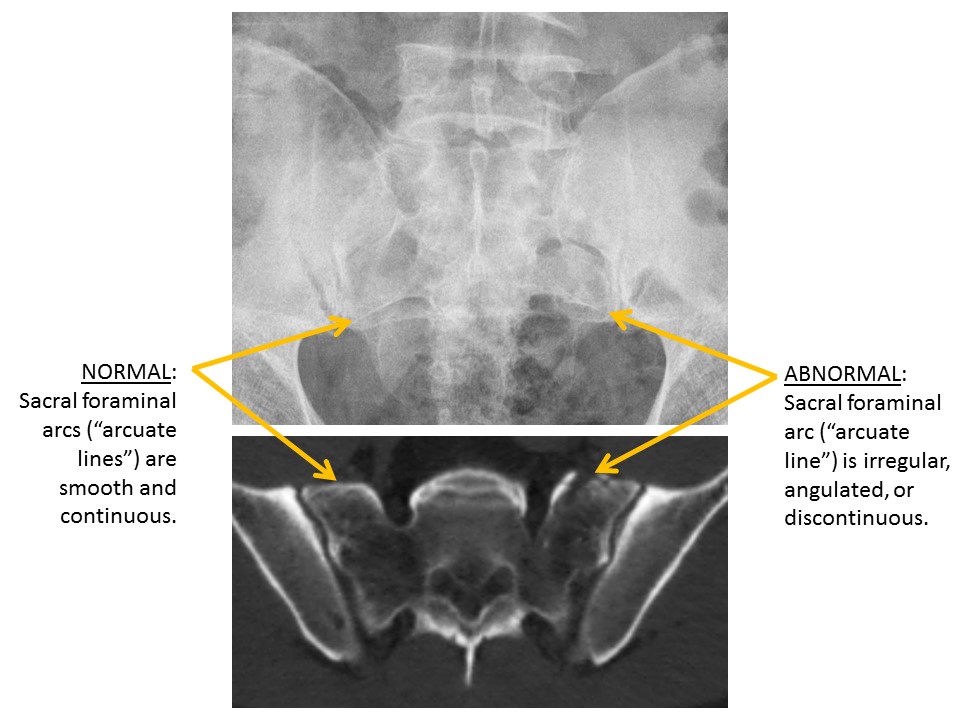

SACRUM and SACROILIAC JOINTS

A fracture is present. [Yes/No]